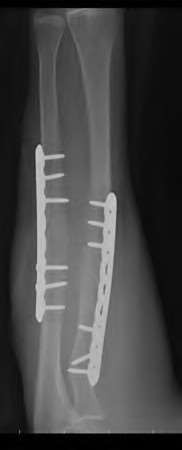

Question 19

A 28-year-old male sustains a closed comminuted tibial shaft fracture.

Two hours post-injury, he develops severe leg pain unyielding to narcotics. His blood pressure is 120/80 mmHg. Intracompartmental pressure monitoring is performed. Based on current guidelines, which measurement dictates an emergent 4-compartment fasciotomy?

Explanation

Acute compartment syndrome is classically defined by tissue hypoperfusion. The absolute compartment pressure is less reliable than the differential pressure (Delta P). A Delta P (Diastolic Blood Pressure minus Compartment Pressure) of less than 30 mmHg is an absolute indication for emergency fasciotomy, as capillary perfusion gradient is lost when tissue pressure approaches the diastolic pressure.